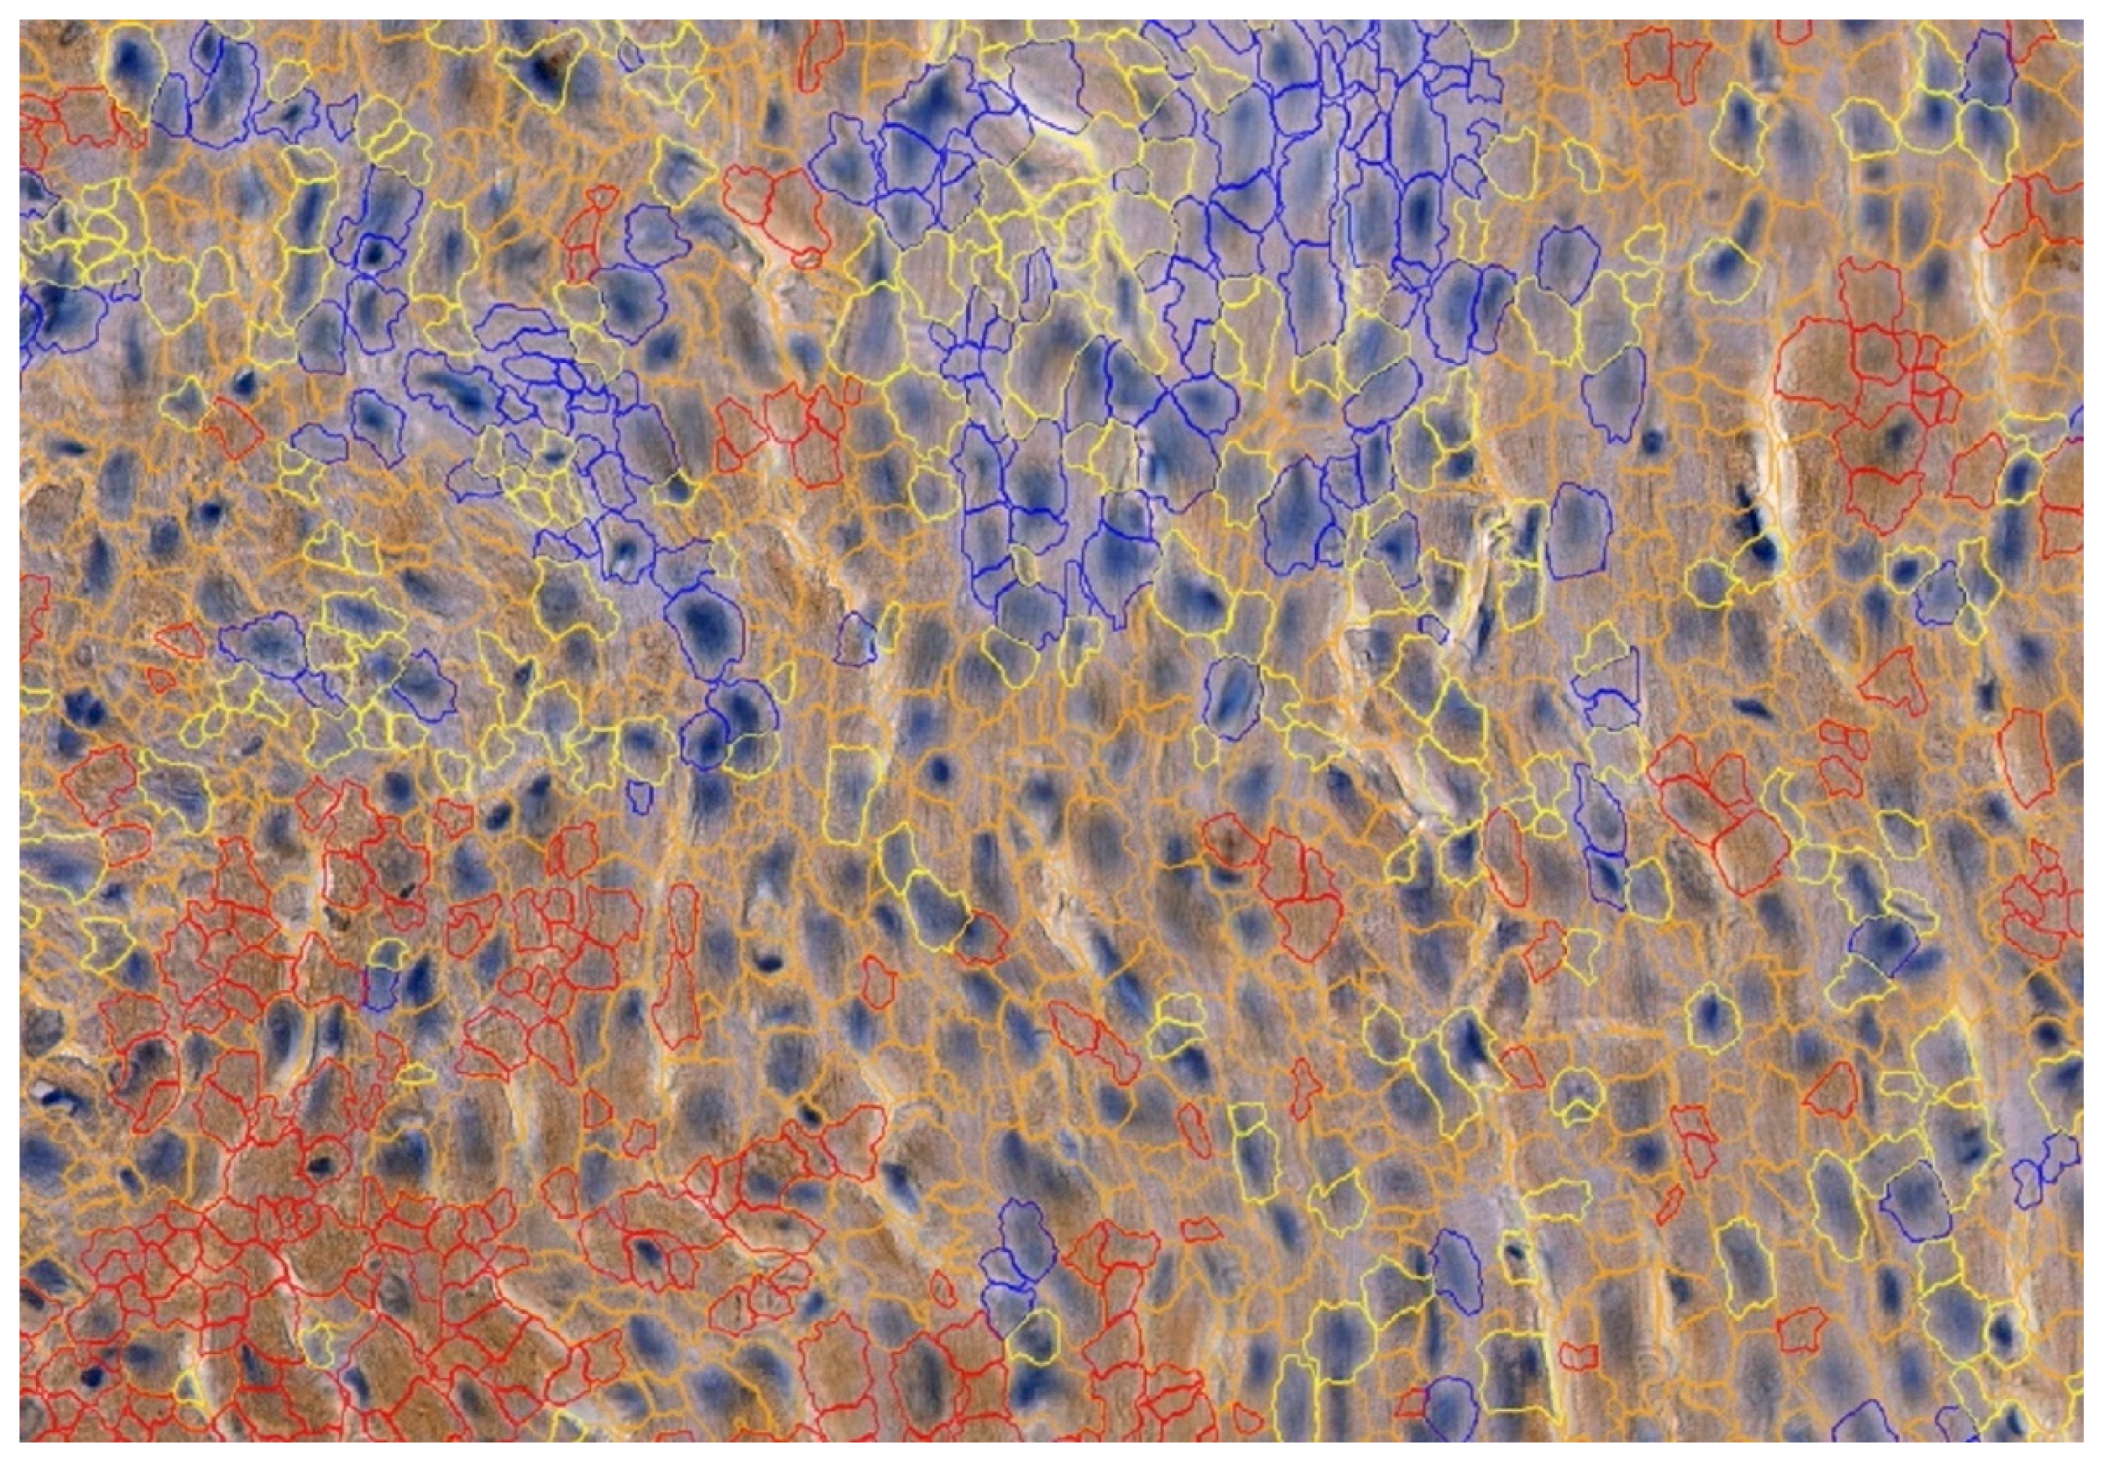

2.3. Morphometry

2.4. Vascular Density

3.2. Morphometry

3.3. Vascular Density